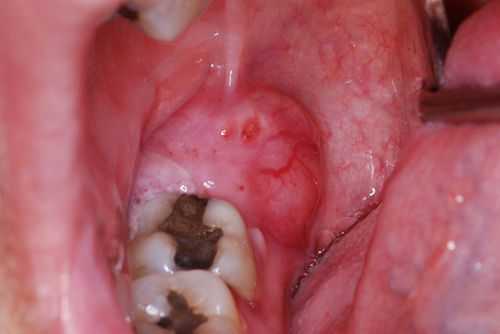

Гнойная форма — одна из самых тяжёлых форм перикоронита. Больной выглядит измученным, о бщее состояние резко ухудшается. Наблюдается стойкое повышение температуры до 38,0 °С , резкая боль при глотании и открывании рта, иррадиация в ухо или висок. Из причинной области в полость рта выделяется гной, причём при пальпации количество отделяемого и болезненные ощущения усиливаются. Регионарные лимфоузлы увеличены и подвижны. Отекает и краснеет не только капюшон и десна, но и нёбно-язычная дужка, слизистая щеки и мягкое нёбо [8] [13] .

Отдельной формой болезни является позадимолярный перикоронит. При этой форме воспаление локализуется ниже уровня коронки. Процесс начинается поверхностно, проникая глубже до вовлечения надкостницы. Если пациент не обращается за помощью своевременно, может возникнуть осложнение в виде ретромолярного абсцесса.